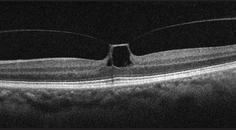

OCT is also valuable in identifying AMD at early stages. Drusen, a hallmark of AMD, are identified on OCT as discrete elevations of the retinal pigment epithelium (RPE) layer at the level of Bruch membrane (Figure). Drusen that form above the RPE are known as reticular pseudodrusen and are a more ominous sign. Patients with this type of drusen are much more likely to progress to advanced disease.11

Figure. OCT findings show numerous medium-sized drusen (>63 μm to ≤125 μm) in a patient with early AMD. No pigmentary abnormalities are present.